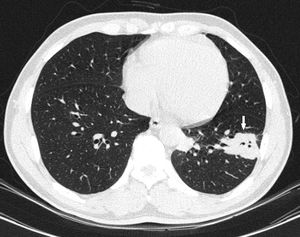

A 45-year-old Colombian male patient, resident of the rural area of southern Colombia (Department of Huila), working in agriculture, with no relevant previous medical history and no known travel abroad, consulted with a two-month history of intermittent left-sided chest pain, of mild-to-moderate intensity, associated with occasional dry cough. The symptoms had worsened in the previous week, with intensification of the pain and unquantified fever. On physical examination, the patient was afebrile, with no evidence of significant abnormalities in the general examination. No abnormalities were found on chest X-ray. In view of the persistence of the patient's pain, a simple and contrasted chest computed tomography (CT) scan was performed, which showed nodular opacity of diffuse distribution in the left lower lobe (Fig. 1).